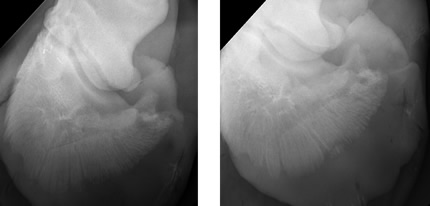

• Typical radiographic findings are focal or generalized demineralization of the solar margin of the distal phalanx and widening of the vascular channels resulting in radiographic loss of the normally smooth border of the solar margin.

• Typically, bone demineralization will occur around the toe margin and irregular bone formation may be seen along the solar margin or the dorsal surface of P3.

• Severe cases of demineralization can weaken the bone margins and cause fractures of the distal phalanx.